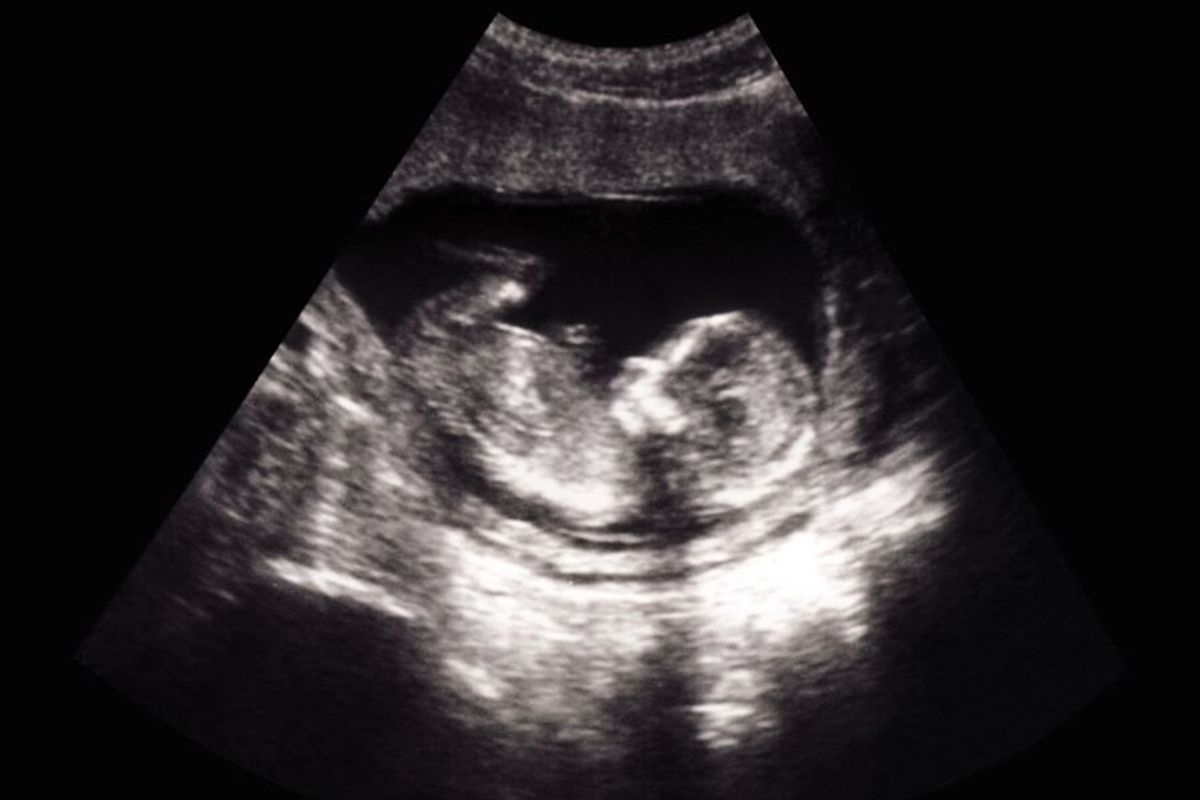

The innovative procedure is performed in utero and guided by ultrasound.

The baby, named Denver Coleman, suffered from vein of Galen malformation (VOGM), a rare abnormality where blood vessels connect directly to veins rather than capillaries, affecting the blood vessels’ ability to carry oxygenated blood from the heart to the brain. The resulting surge of blood pressure can lead to major health issues like congestive heart failure, losing brain tissue or an enlarged head.According to a statement from the American Heart Association (via Newsroom) VOGM affects an estimated 1 in 60,000 births. The current standard treatment happens after birth, where surgeons close off direct artery-to-vein connections in the brain to block the excess blood flow. However, this operation is highly risky and not always successful, not to mention that by the time the baby is born, severe brain damage might have already occurred, making it too late to prevent lifelong or even fatal damage. Conversely, the new procedure, which was detailed in the journal Stroke, uses an in-utero, ultrasound-guided utero surgery designed to reduce the aggressive blood flow